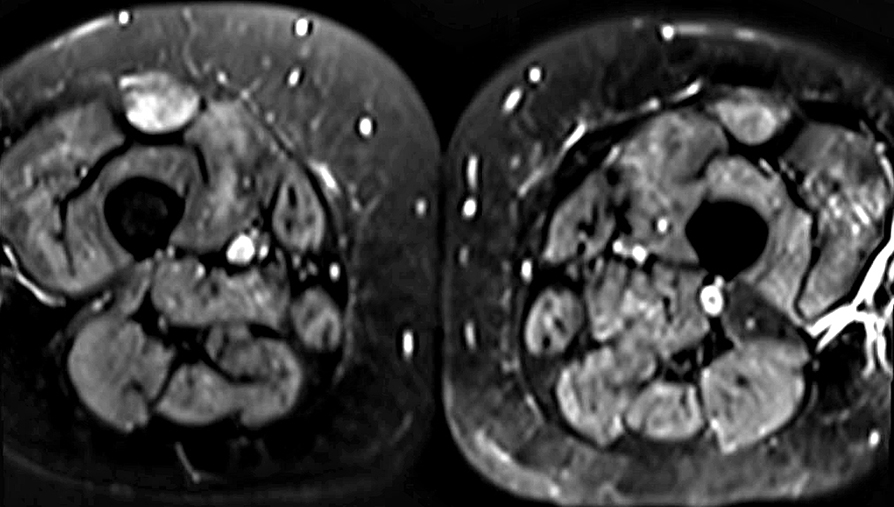

SMA 5q, Type III - IV

SMN1 0 copies; SMN2 4 copies

T1 images     From: F Fatehi